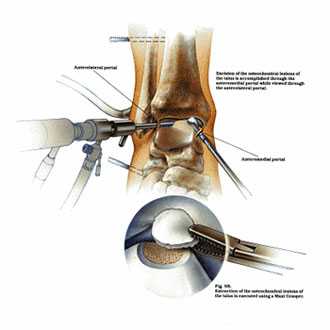

Благодаря современному оснащению нашей клиники сегодня мы можем отказаться от травматичных открытых операций на голеностопном суставе. На замену им пришла артроскопия.

Суть вмешательства проста. Через небольшие разрезы врач вводит в полость сустава специальную трубку, снабженную видеокамерой. Камера дает необходимый обзор, позволяя с высокой точностью проводить операцию. В ходе артроскопии медик либо удаляет некротизированный кусок костной ткани, чтобы он не доставлял человеку неудобств, либо, если некроз не окончательно поразил участок кости, крепит доставляющую неудобства часть к основному массиву с помощью специальных скобок или винтов.

Артроскопия, метод выбора для пациентов с рассекающим остеохондритом. Операция менее травматична, восстановление после нее проходит легче и быстрее.

Мозаичная хондропластика выполняется артроскопически или открыто, через небольшой кожный разрез в области голеностопного сустава. Если требуется небольшой трансплантат для заполнения дефекта хряща, то его забирают из переднего не нагружаемого отдела блока таранной кости. Однако чаще, костно-хрящевой цилиндр (трансплантат) берут из не нагружаемой зоны мыщелка бедра коленного сустава. При этом забор костно-хрящевого столбика из коленного сустава производится с применением артроскопической технологии через проколы кожи.

По завершении подготовки ложа таранной кости, хирург перемещает астроскоп в коленный сустав, где выполняется забор остеохондральных трансплантатов из мыщелков бедра.

Трансплантаты забираются с помощью трубчатых полых сверил, которые обеспечивают забор трансплантата точного диаметра и длины.

Далее переходят обратно на голеностопный суставе, где в области дефекта хряща таранной кости, специальными сверлами формируется костный каналы соответствующий трансплантатам из коленного сустава по длине и диаметру. В завершении трансплантаты взятые из коленного сустава впрессовывается в сформированный в таранной кости каналы и моделируется по уровню суставной площадки.